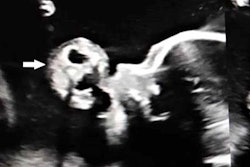

Computed tomography scan of a peritonsillar abscess in a 21-year-old man. All images courtesy of BMJ Case Reports.Simple procedure, complicated times

A computed tomography (CT) scan confirmed the abscess. The man was admitted to the hospital and given high-dose intravenous antibiotics and steroid therapy to manage the abscess and to limit healthcare workers' exposure to SARS-CoV-2, they wrote.